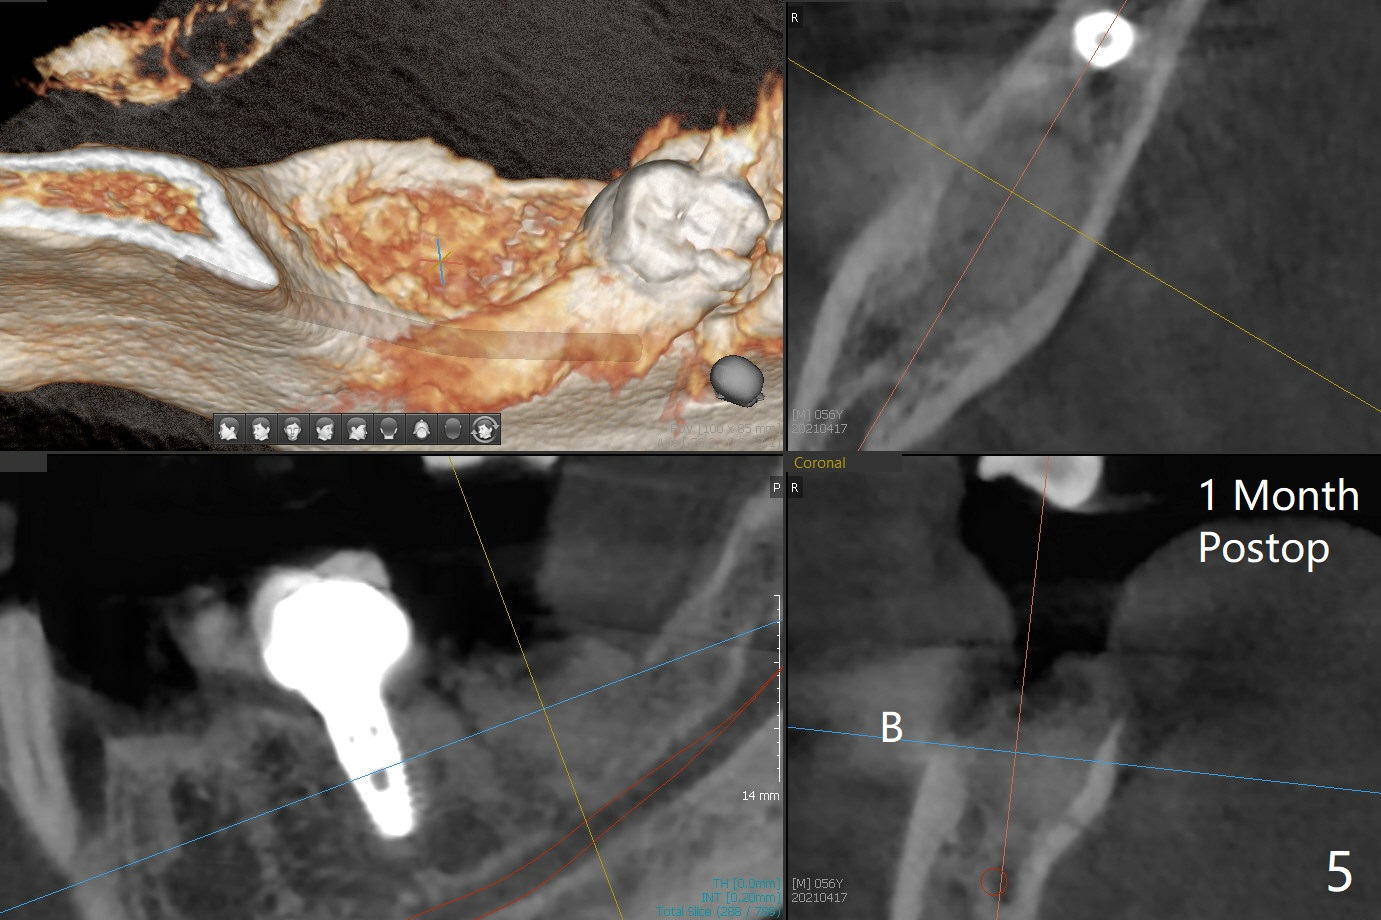

56岁男严重牙周炎,要求拔除右下7(图一),病人特别提出彻底清除炎性组织,GEM21S与皮质骨粉调袢5分钟后放置清创的牙槽窝(图二:*),覆盖Cytoplast,4-0 PTFE缝合。术后一个月膜游离(图三),撤线(缝线不是故意穿过膜)后,膜去除,下面骨粉好像稳定(图四至六)。